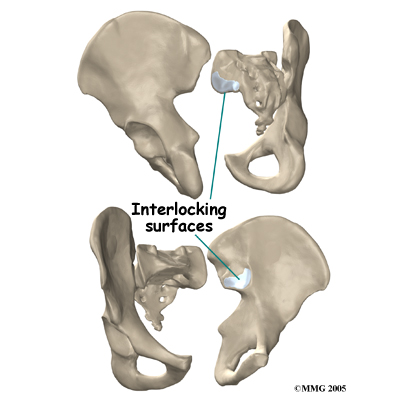

The SI joint is one of the larger joints in the body. The surface of the joint is wavy and similar to the way Legos fit together. Very little motion occurs in the SI joint. The motion that does occur is a combination of sliding, tilting and rotation. The most the joint moves in sliding is probably only a couple of millimeters, and may tilt and rotate two or three degrees.